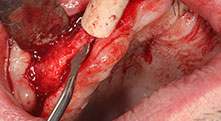

Bratu: Preferimos realizar las osteotomías en la línea oblicua externa de la cara posterior del maxilar inferior, y no en la región situada entre los orificios. Tras realizar una incisión en los tejidos blandos, utilizamos las nuevas sierras para definir el contorno de la osteotomía. De este modo, conseguimos una preparación completa en prácticamente el 80 por ciento de los casos. Por otro lado, en algunas ocasiones también utilizamos otros insertos piezoquirúrgicos, así como un cincel para mover el injerto. Para nosotros, esta es una técnica de intervención muy eficaz.

Bratu: Nos gusta utilizar la técnica de sándwich para realizar aumentos en la cara lateral del maxilar inferior. En este procedimiento, se utiliza la sierra piezoquirúrgica para preparar una tapa ósea, mientras que el fragmento crestal se fija con microtornillos. Entre medias, colocamos una combinación de hueso autólogo y material óseo adicional xenógeno. Y con ello obtenemos un rendimiento muy fiable. Asimismo, en los ranurados de la cresta alveolar del maxilar inferior, nunca se puede prescindir de cortes verticales suficientemente dimensionados, pues, de lo contrario, los huesos pueden fracturarse fácilmente.